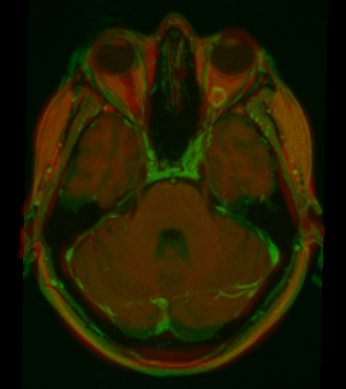

MartaPeroni (talk | contribs) (Screenshot of overlay between warped atlas and original MRI of a patient with trigeminal neuralgia) |

Screenshot of overlay between warped atlas and original MRI of a patient with trigeminal neuralgia

| current | 12:35, 22 June 2009 | 346 × 389 (176 KB) | MartaPeroni (talk | contribs) | Screenshot of overlay between warped atlas and original MRI of a patient with trigeminal neuralgia |